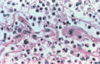

A diabetic patient presents to your clinic with hemoptysis. Biopsy of this lung is shown below. What is causing his symptoms?

Note the many dichotomous branching hyphae with septation and 45 degree angle of branching in the biopsy. This is invasive aspergillus. It gets into the blood vessels and causes bleeding (shown below).